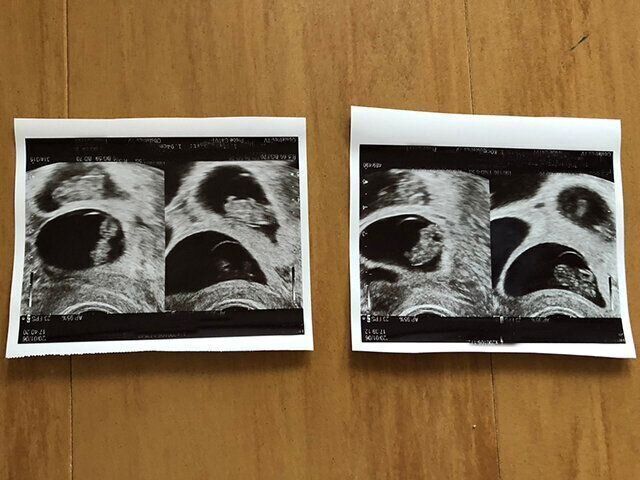

「次の週は胎嚢が2つ、その次の週には胎嚢が4つと、だんだん増えていきました。最終的に4つ子だということがわかった時はとても嬉しかったです。不妊治療中は『もしかしかたら私には子どもができないかもしれない』と自信を失っていたので、子どもができたことに嬉しさしかありませんでした。夫も『嬉しい!!』と一緒に喜んでくれました。